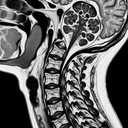

МРТ хребта

Магнітно-резонансна томографія (МРТ) хребта — це неінвазивний діагностичний метод, який використовує магнітні поля та радіохвилі для отримання детальних зображень хребта та навколишніх тканин. Це дослідження допомагає виявити такі проблеми, як грижі міжхребцевих дисків, звуження спинномозкового каналу, пухлини, інфекції та аномалії в структурі хребта. **Переваги МРТ хребта:** - Надає чіткі зображення м'яких тканин, включаючи спинний мозок, нерви та диски...

МРТ шийного відділу хребта шиї

МРТ шийного відділу хребта – це неінвазивний метод діагностики, що використовує магнітні поля та радіохвилі для отримання детальних зображень. Це дослідження допомагає виявити різні захворювання та патології, такі як: 1. **Грижі міжхребцевих дисків** – виявлення випинання дисків, що можуть здавлювати нерви...